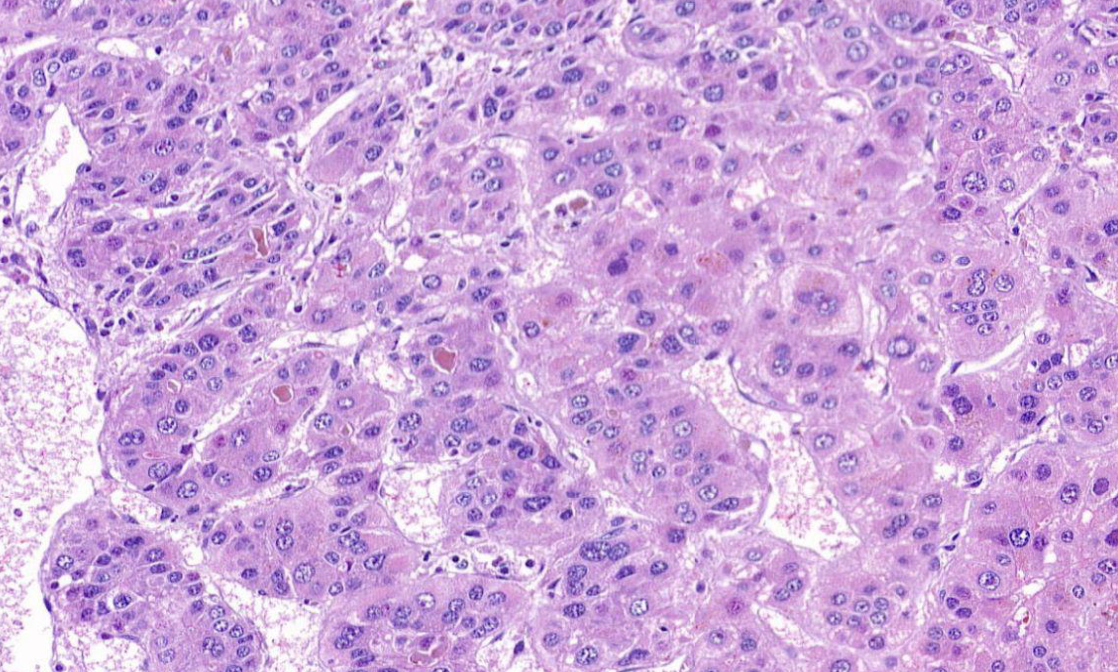

Diagnose?

Lobuläres Mamma-CA